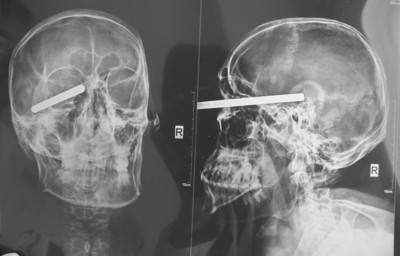

一个士兵在战场上被一块弹片击中头部,昏迷了几天。取出弹片后,人清醒了,但不久后左臂开始麻木,讲话颠三倒四,坐在床上一个人也会发笑。医生诊断为脑外伤神经病。

神经病指人的神经系统的某些部位受感染、中毒、外伤、肿瘤、血管病变、变性等的侵袭,造成损害与病变,引起麻木、疼痛、瘫痪、抽搐、昏迷等症状的疾病。一般来说,病人的心理活动并没有显著异常。而有些脑部器质性病变,既有神经系统受损害的症状,又有心理活动和行为的异常,要诊断是否患神经病,需视神经系统是否有实质性病变。在神经系统解剖中可以找到病变的部位,即器质性变化。如坐骨神经痛,这是下肢一根坐骨神经发生病变或受到压迫造成的。继发性的癫痫病患者,尽管也有一些精神病患者的症状,但多是脑部肿瘤、闹脓疮、脑外伤、脑寄生虫、脑血管硬化、脑萎缩以及一系列的脑器质性病变而引起的一种神经病。